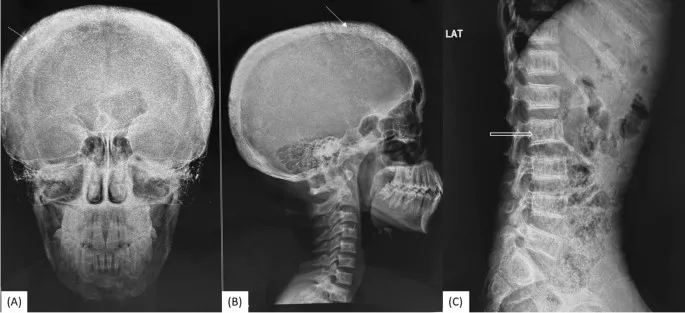

- Bones: Osteitis fibrosa cystica (OFC; "brown tumors"), subperiosteal bone resorption (e.g., phalanges), "salt-and-pepper" skull.